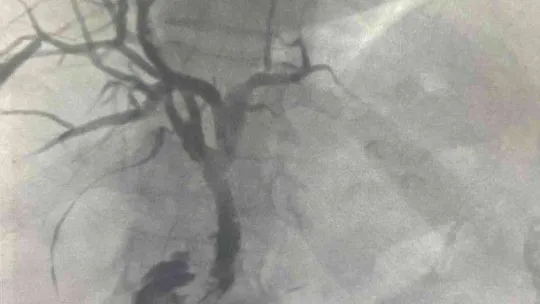

Prof. Dr. Ercan Kocakoç, bu yeni yöntemin tıp literatürüne Radyofrekans (RF) ablasyon olarak geçtiğini belirtti. Başta karaciğer olmak üzere vücudun birçok bölgesindeki tümörlerin ultrason, tomografi gibi görüntüleme yöntemlerinin kılavuzluğunda yakılarak tedavi edebilen, girişimsel radyolojik bir yöntem olduğunu söyledi. Prof. Dr. Ercan Kocakoç, önce safra kanalı içerisine basitçe ince plastik bir hortum yerleştirilerek, biriken safra sıvısının dışarıya alındığını dile getirerek, “Tümörün olduğu bölgedeki darlık, bir tel yardımıyla geçilebilirse önce balon ile bu bölge genişletilmeye çalışılır. Sonrasında ise stent denilen ince tellerden örülü metalik bir küçük borucuk yerleştirilerek dışarıda hortum olmadan safranın on iki parmak barsağına akması sağlanır” dedi.

Prof. Dr. Ercan Kocakoç ayrıca safra yolu kanserlerinin tedavisinde Endobiliyer RF ablasyon yöntemi ile de safra kanalı içerisindeki tümörün RF ablasyon ile yakıldığını kaydederek, “Bu yöntemde safra kanalındaki darlığın balon ile açılması, safra kanalı içerisinden RF (radyofrekans) ablasyon ile tümörün yakılması ve safra kanalına metalik stent yerleştirilmesi aşamaları vardır. Bu işlem safranın on iki parmak bağırsağına akmasını sağlayarak sarılıksız daha uzun bir ömür geçirilmesine katkı sağlar” şeklinde konuştu.